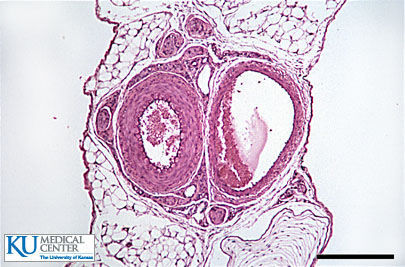

Transitional (stratified)